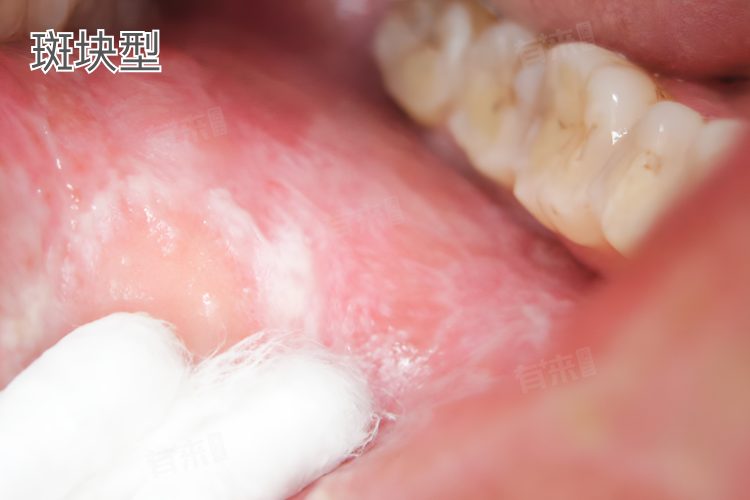

斑块型

- 表现为口腔黏膜上出现白色或灰白色的均质型斑块,形状多不规则,大小差异较大,有的可能只有指甲盖大小,有的则可以占据较大面积的黏膜区域,斑块表面相对比较光滑,质地稍硬,边界通常较清晰,与周围正常黏膜有明显的分界。

- 这种斑块一般是长期存在且比较顽固,不易消退,常见于颊黏膜、舌背等部位,患者可能会因担心是其他严重疾病而产生心理压力。